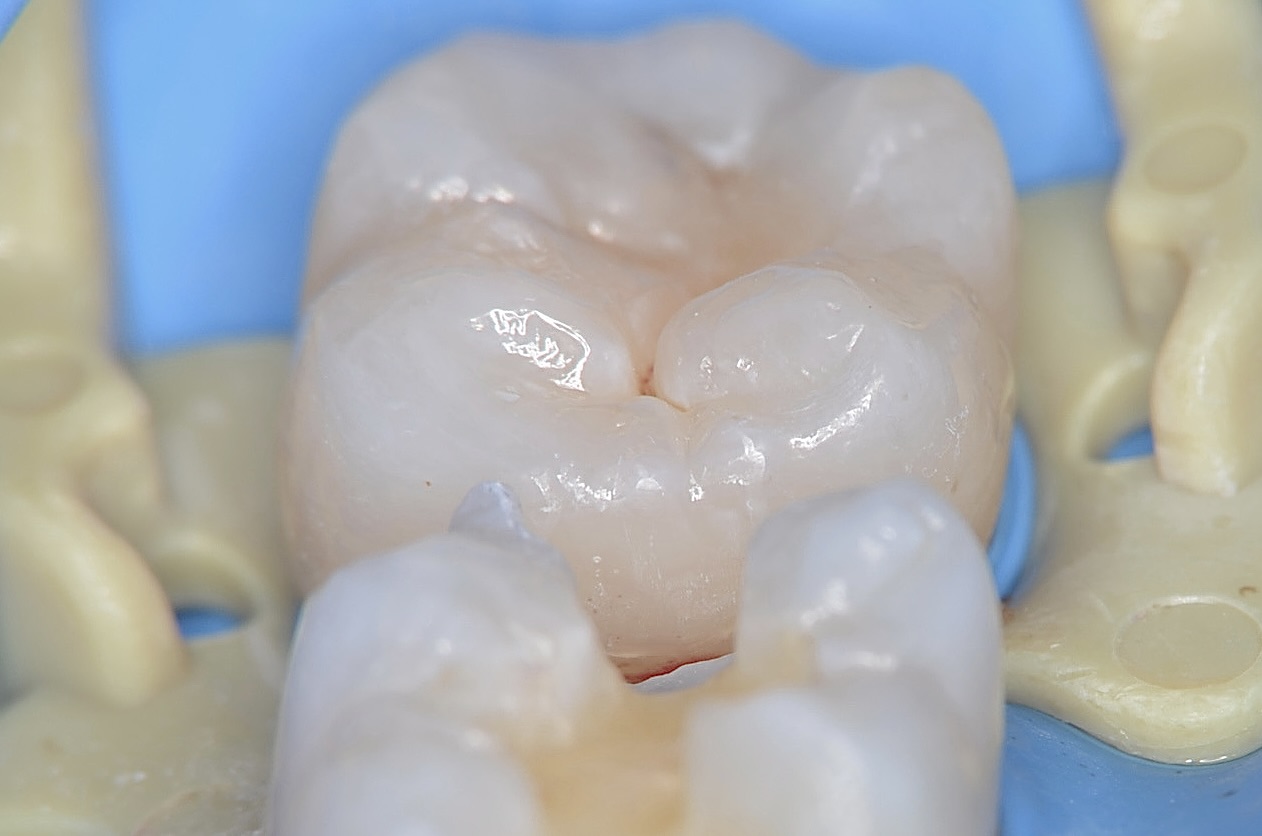

6番形成終了

象牙質の部分はIDSと言って、レジンコーティングしていますので、滲みにくくなります。また接着効果を高めます。 -

色合わせ

ジルコニアインレーの色合わせをしたのちに、型取りします。 -